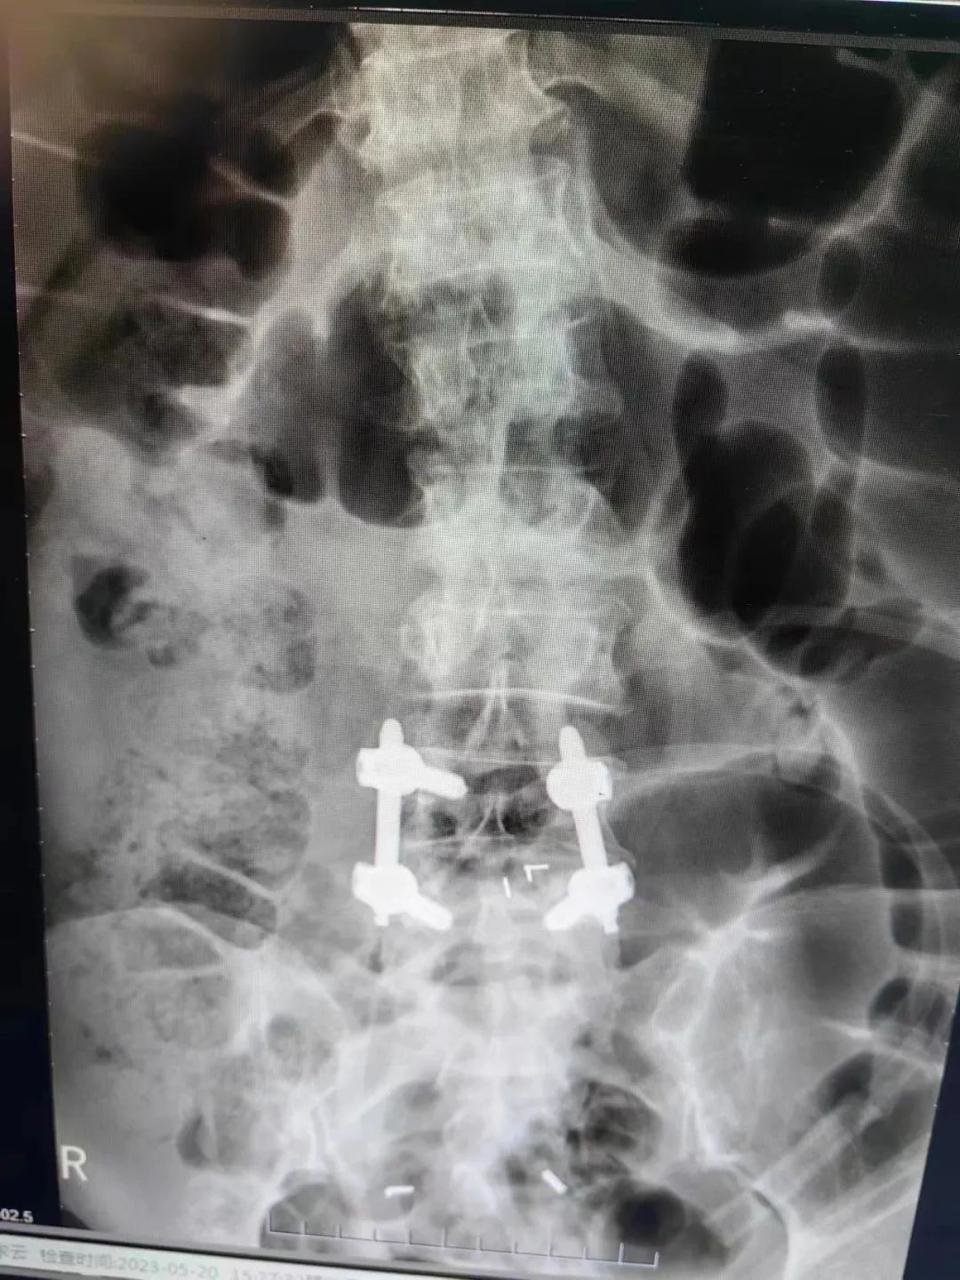

骨科二十二病室(脊柱外科)主任陈立带领团队详细检查评估后,5月19日,顺利为杨阿姨进行后路腰4-5椎弓根螺钉内固定+椎间融合器植入植骨融合手术。